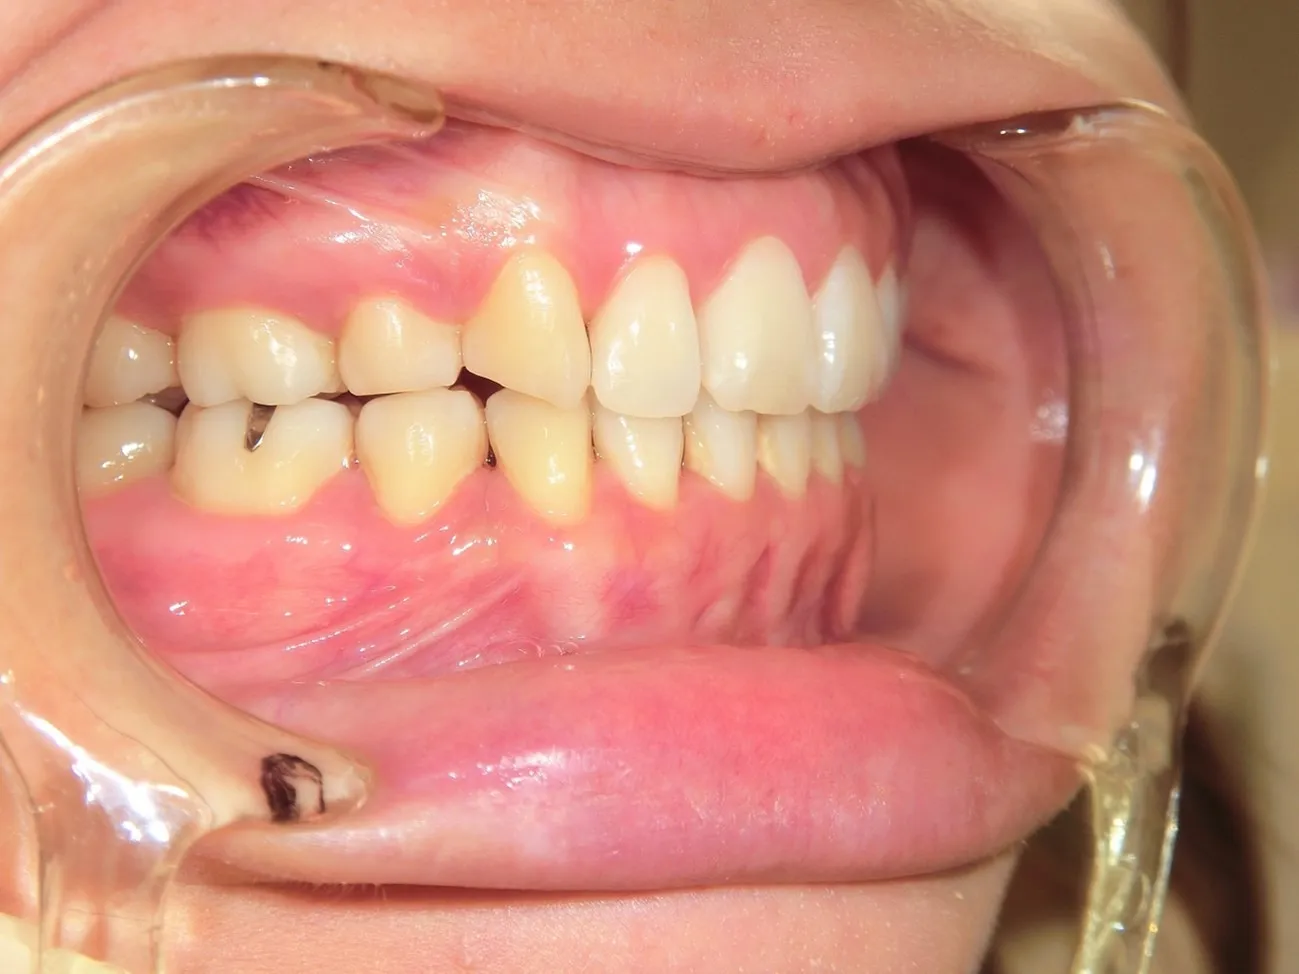

施術を検討されている方に様々なケースの施術前後の違いをご確認いただけるよう、インプラントやインビザラインでの矯正の症例を画像も用いて一覧にして載せております。「ずれている前歯を揃えたい」「受け口を直したい」「抜けた歯をキレイに整えたい」など、様々なご相談を承り、ご予算や仕上がりのご要望はもちろんのこと、長期的な口腔の健康維持も考慮したプランをご提案いたします。